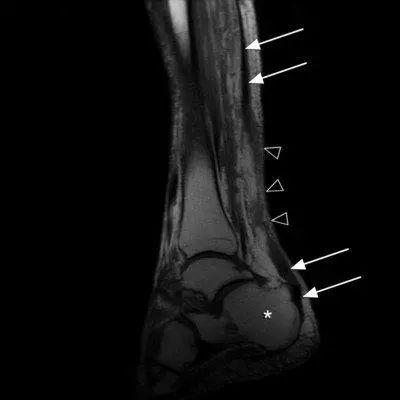

那么想要再确定的判断跟腱断裂与否要做什么检查呢?超声或者核磁共振。

正后方看,可以看到粗黑长的跟腱再中间变得不连续了

白色箭头是跟腱 三角是断裂处

白色箭头是跟腱的断裂部位